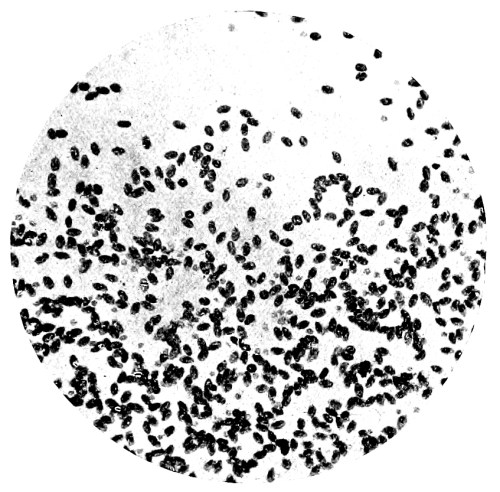

8. Measurement of Blood Corpuscles (human) 97

9. Measurement of Blood Corpuscles (sheep) 97